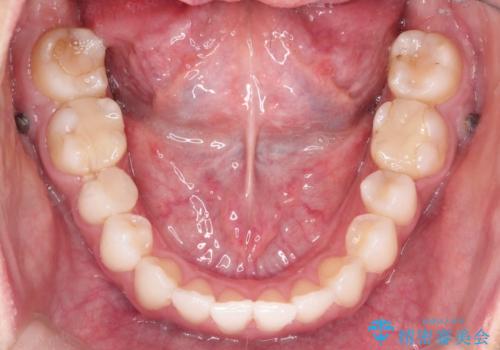

- 前歯の凸凹を主訴に来院されました。

非抜歯の範囲でできるだけ前歯を下げることを希望されたため、IPRと臼歯部の遠心移動を行い治療を行いました。当初はインビザラインで治療を行っておりましたが、使用時間を十分に確保できないことで途中からワイヤーを使用しております。

インビザラインは使用時間が不足し治療計画に支障が出る場合、ワイヤーを使用せざる得ない場合があります。(追加の治療費が必要)